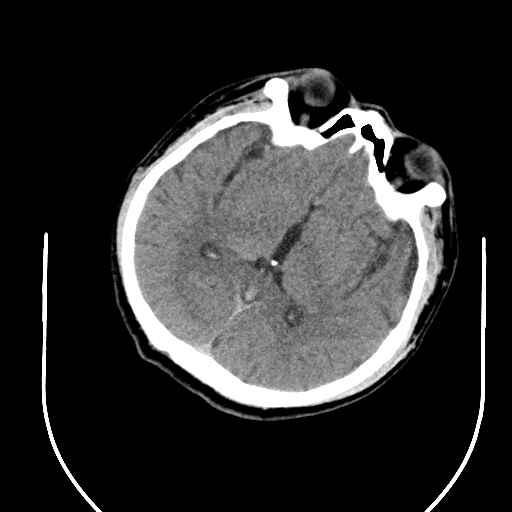

入院头CT

急诊予以静脉溶栓,同时完善头颈CTA+CTP、MIStar相关检查

结合CTA结果,提示左侧颈内动脉起始部至颈内动脉末端未见显影,起始部成鼠尾征改变,前交通动脉开放,双侧大脑中动脉显影良好。MIStar图像提示核心梗死灶和缺血半暗带较小,但是MTT提示左侧大脑中动脉流域区明显延长。

考虑此次发病可能为左侧颈内动脉慢性狭窄基础上出现急性闭塞,导致左侧大脑半球血流量受影响,幸运的是前交通动脉开放,受到对侧代偿供血,左侧大脑半球未出现急性大面积缺血,向患者家属交代后,家属同意暂静脉溶栓观察。

静脉溶栓过程患者症状逐渐减轻,构音障碍和右侧肢体活动不灵均有缓解,NIHSS评分降到2分。就在溶栓快结束时,患者突然症状再次加重,NIHSS评分10分,复查头CT未见出血。结合之前影像,不除外左侧颈内动脉急性闭塞形成血栓后脱落可能,立即启动急诊介入治疗。